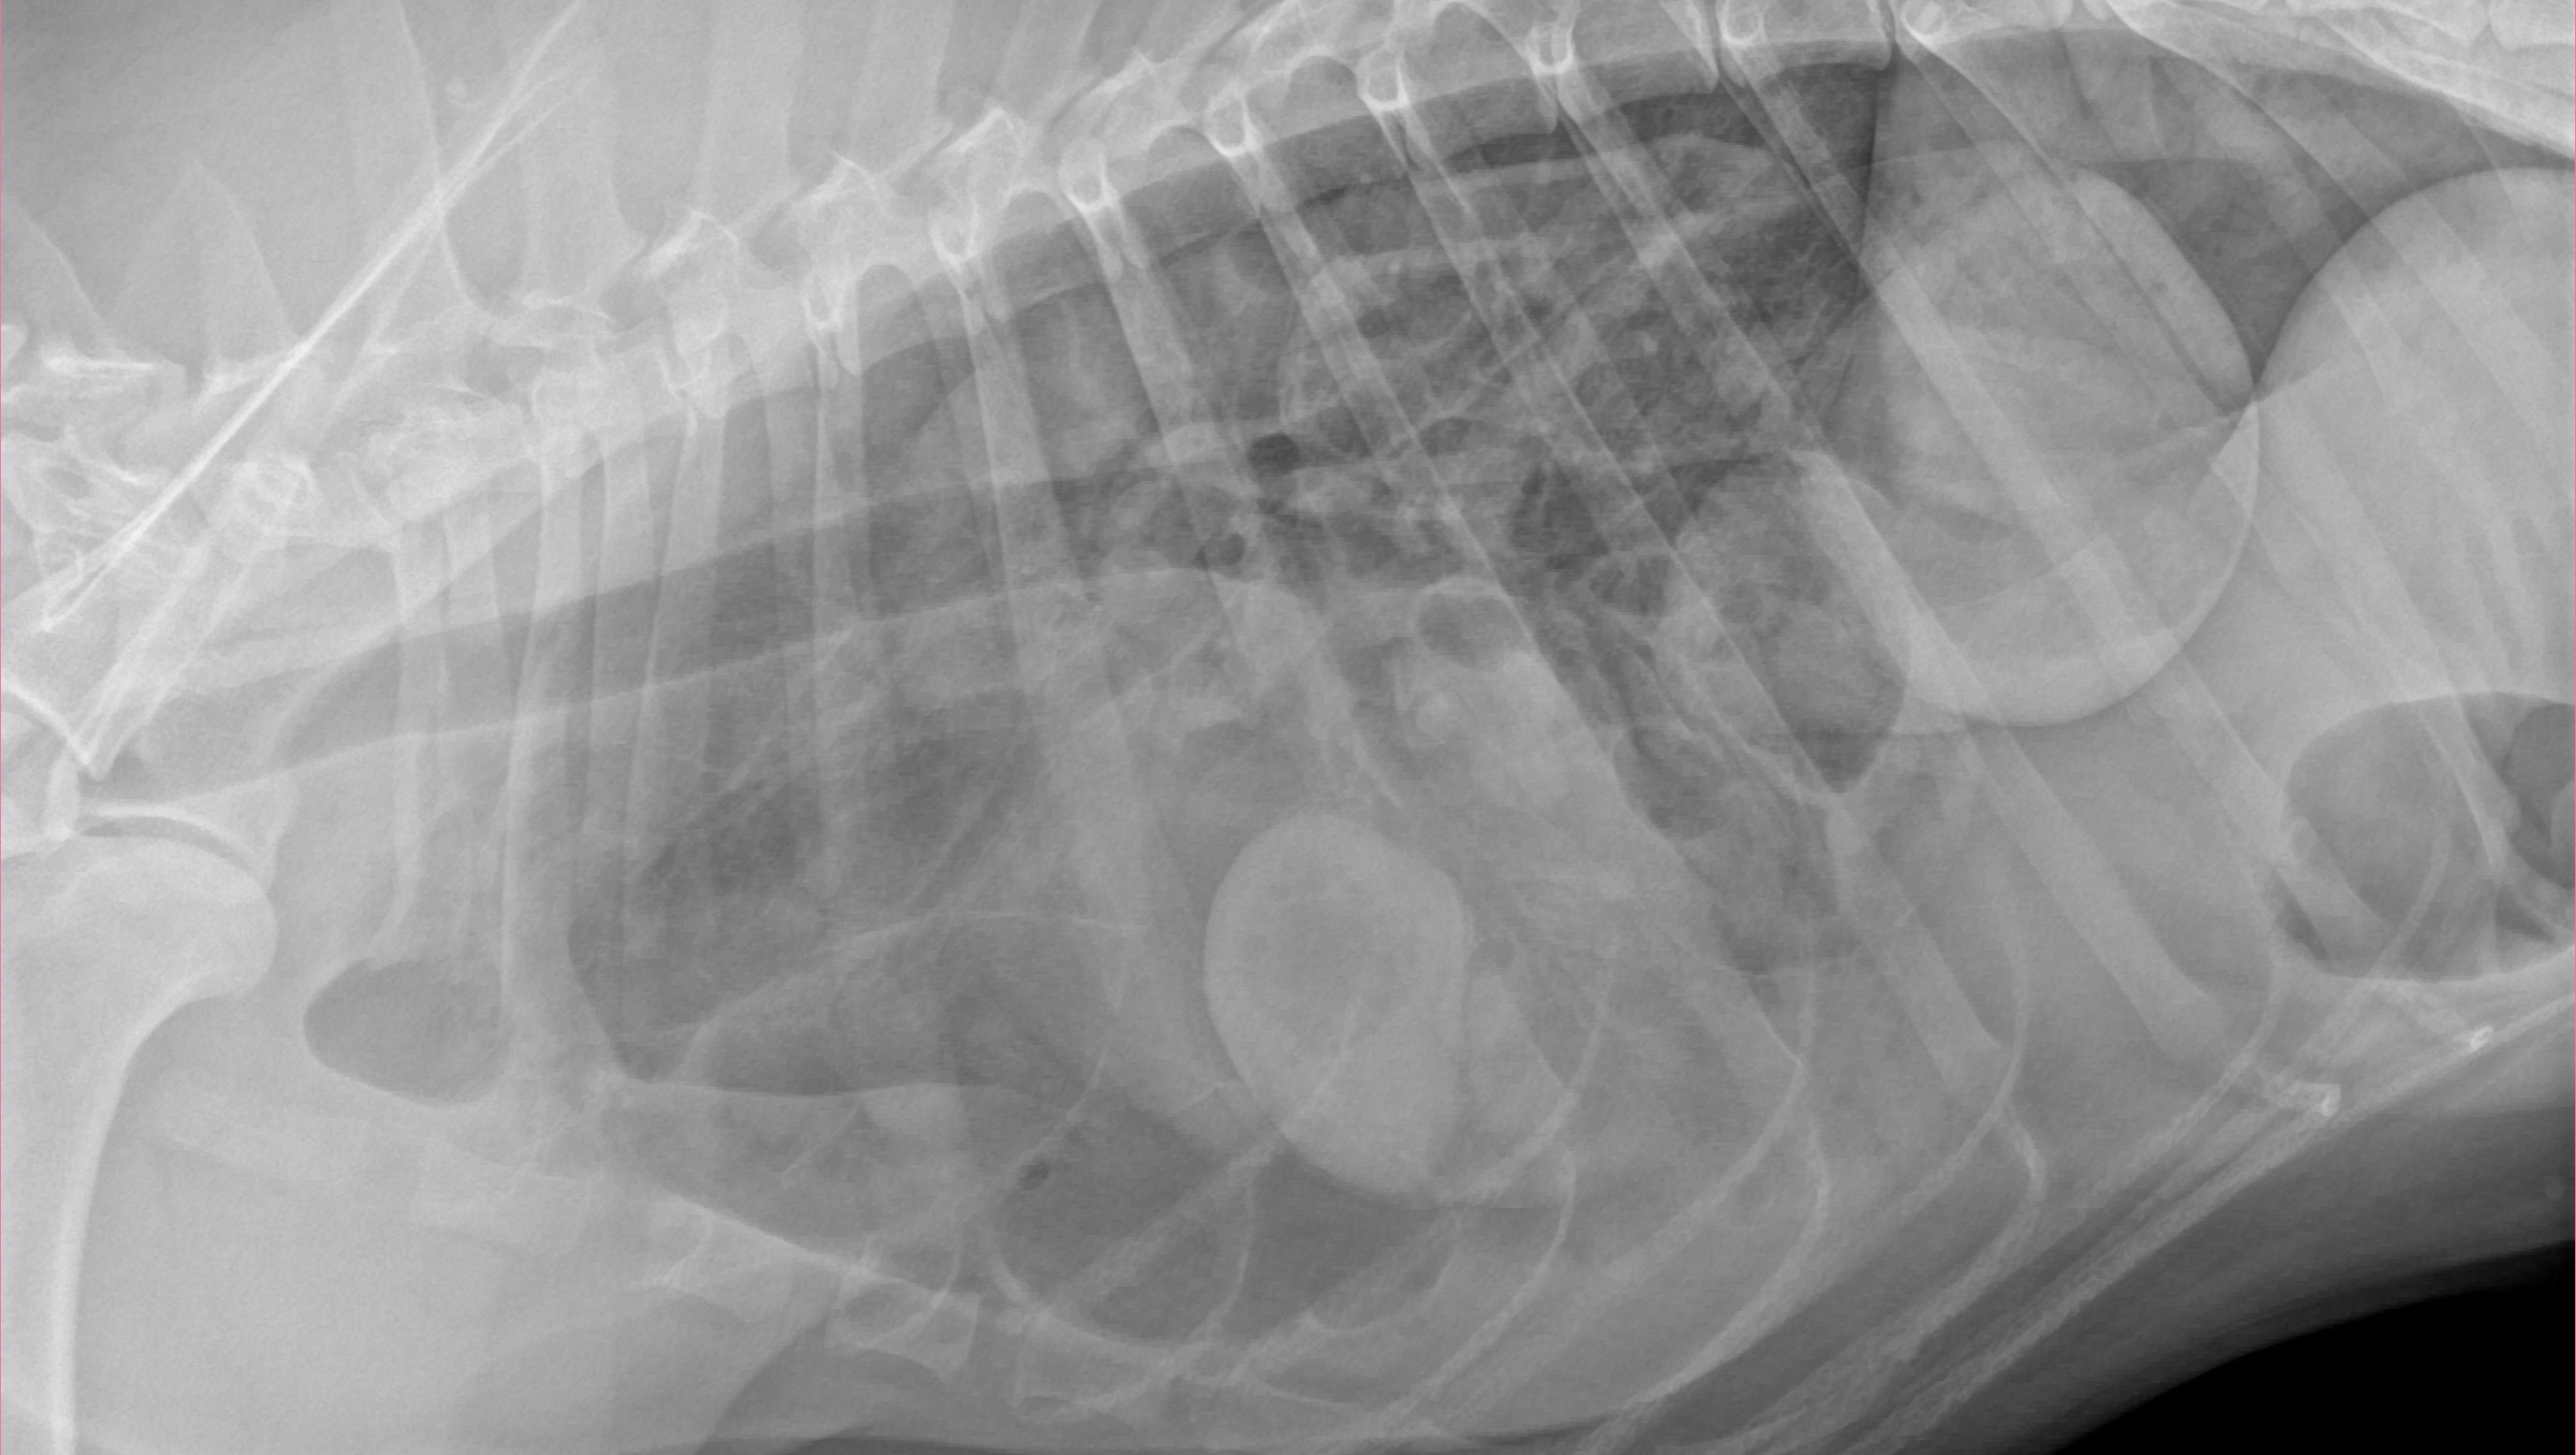

Although our hearts are over joyed to have our boy back, we just received terrible news. It looks like Romulus may have been hit by a car on his adventure away from home and needs emergency surgery to repair a diaphragmatic hernia. We are on our way to UC Davis as we speak to have a consult with a surgeon who has quoted roughly 3-5k for the initial visit and stabilization with another 10-15k for the actually surgery itself. Thankfully Romulus does have insurance, however, they will not cover the entire cost so we are asking for a little bit of help from whoever is willing and able to assist us with our baby boys veterinary bills.